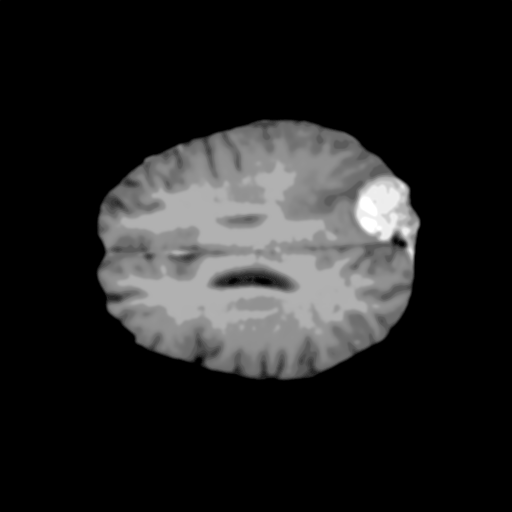

Extensive experiments have been performed in the current setup, and experimental outcomes are reported with the demonstration of numerical and statistical analyses using the proposed QFS-Net, QIS-Net [39], convolutional U-Net [18] and Residual U-Net (URes-Net) architectures [20]. The human expert segmented skull-tripped contrast enhanced DSC brain MR input image slices of size and ROIs are provided in Figure 5 as samples. The demonstration of QFS-Net segmented images followed by the essential post-processed outcome on the slice no. for class level with four distinct activation schemes () are shown in Figure 6. It is evident from the experimental data provided in Table LABEL:tab1 that the proposed QFS-Net performs optimally for the -connected quantum fuzzy pixel information heterogeneity assisted activation () with and gray scale set in comparison with other thresholding schemes and gray scale sets under the four evaluation parameters () [44]. The segmented tumors obtained using the proposed self-supervised procedure under class transition levels with four different thresholding schemes , , and are demonstrated in Figures 7- 8 for the class boundary sets and [39], respectively. The segmented images using the remaining two class boundary sets ( and ) [39] are provided in the supplementary materials section. The segmented ROIs describing the whole tumor region after the masking procedure using QIS-Net, U-Net and URes-Net are also reported in Figure 9.